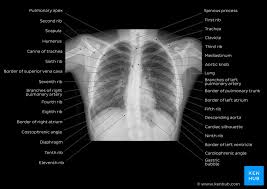

Normal Chest X Ray With Diaphragmatic Slips When The Lungs Are Hyperexpanded It Is Important Not To Confuse Blunting Of A Costophre Radiology X Ray Vision Eye

Chest X Rays Physiopedia

Normal Chest X Ray Anatomy Tutorial Kenhub